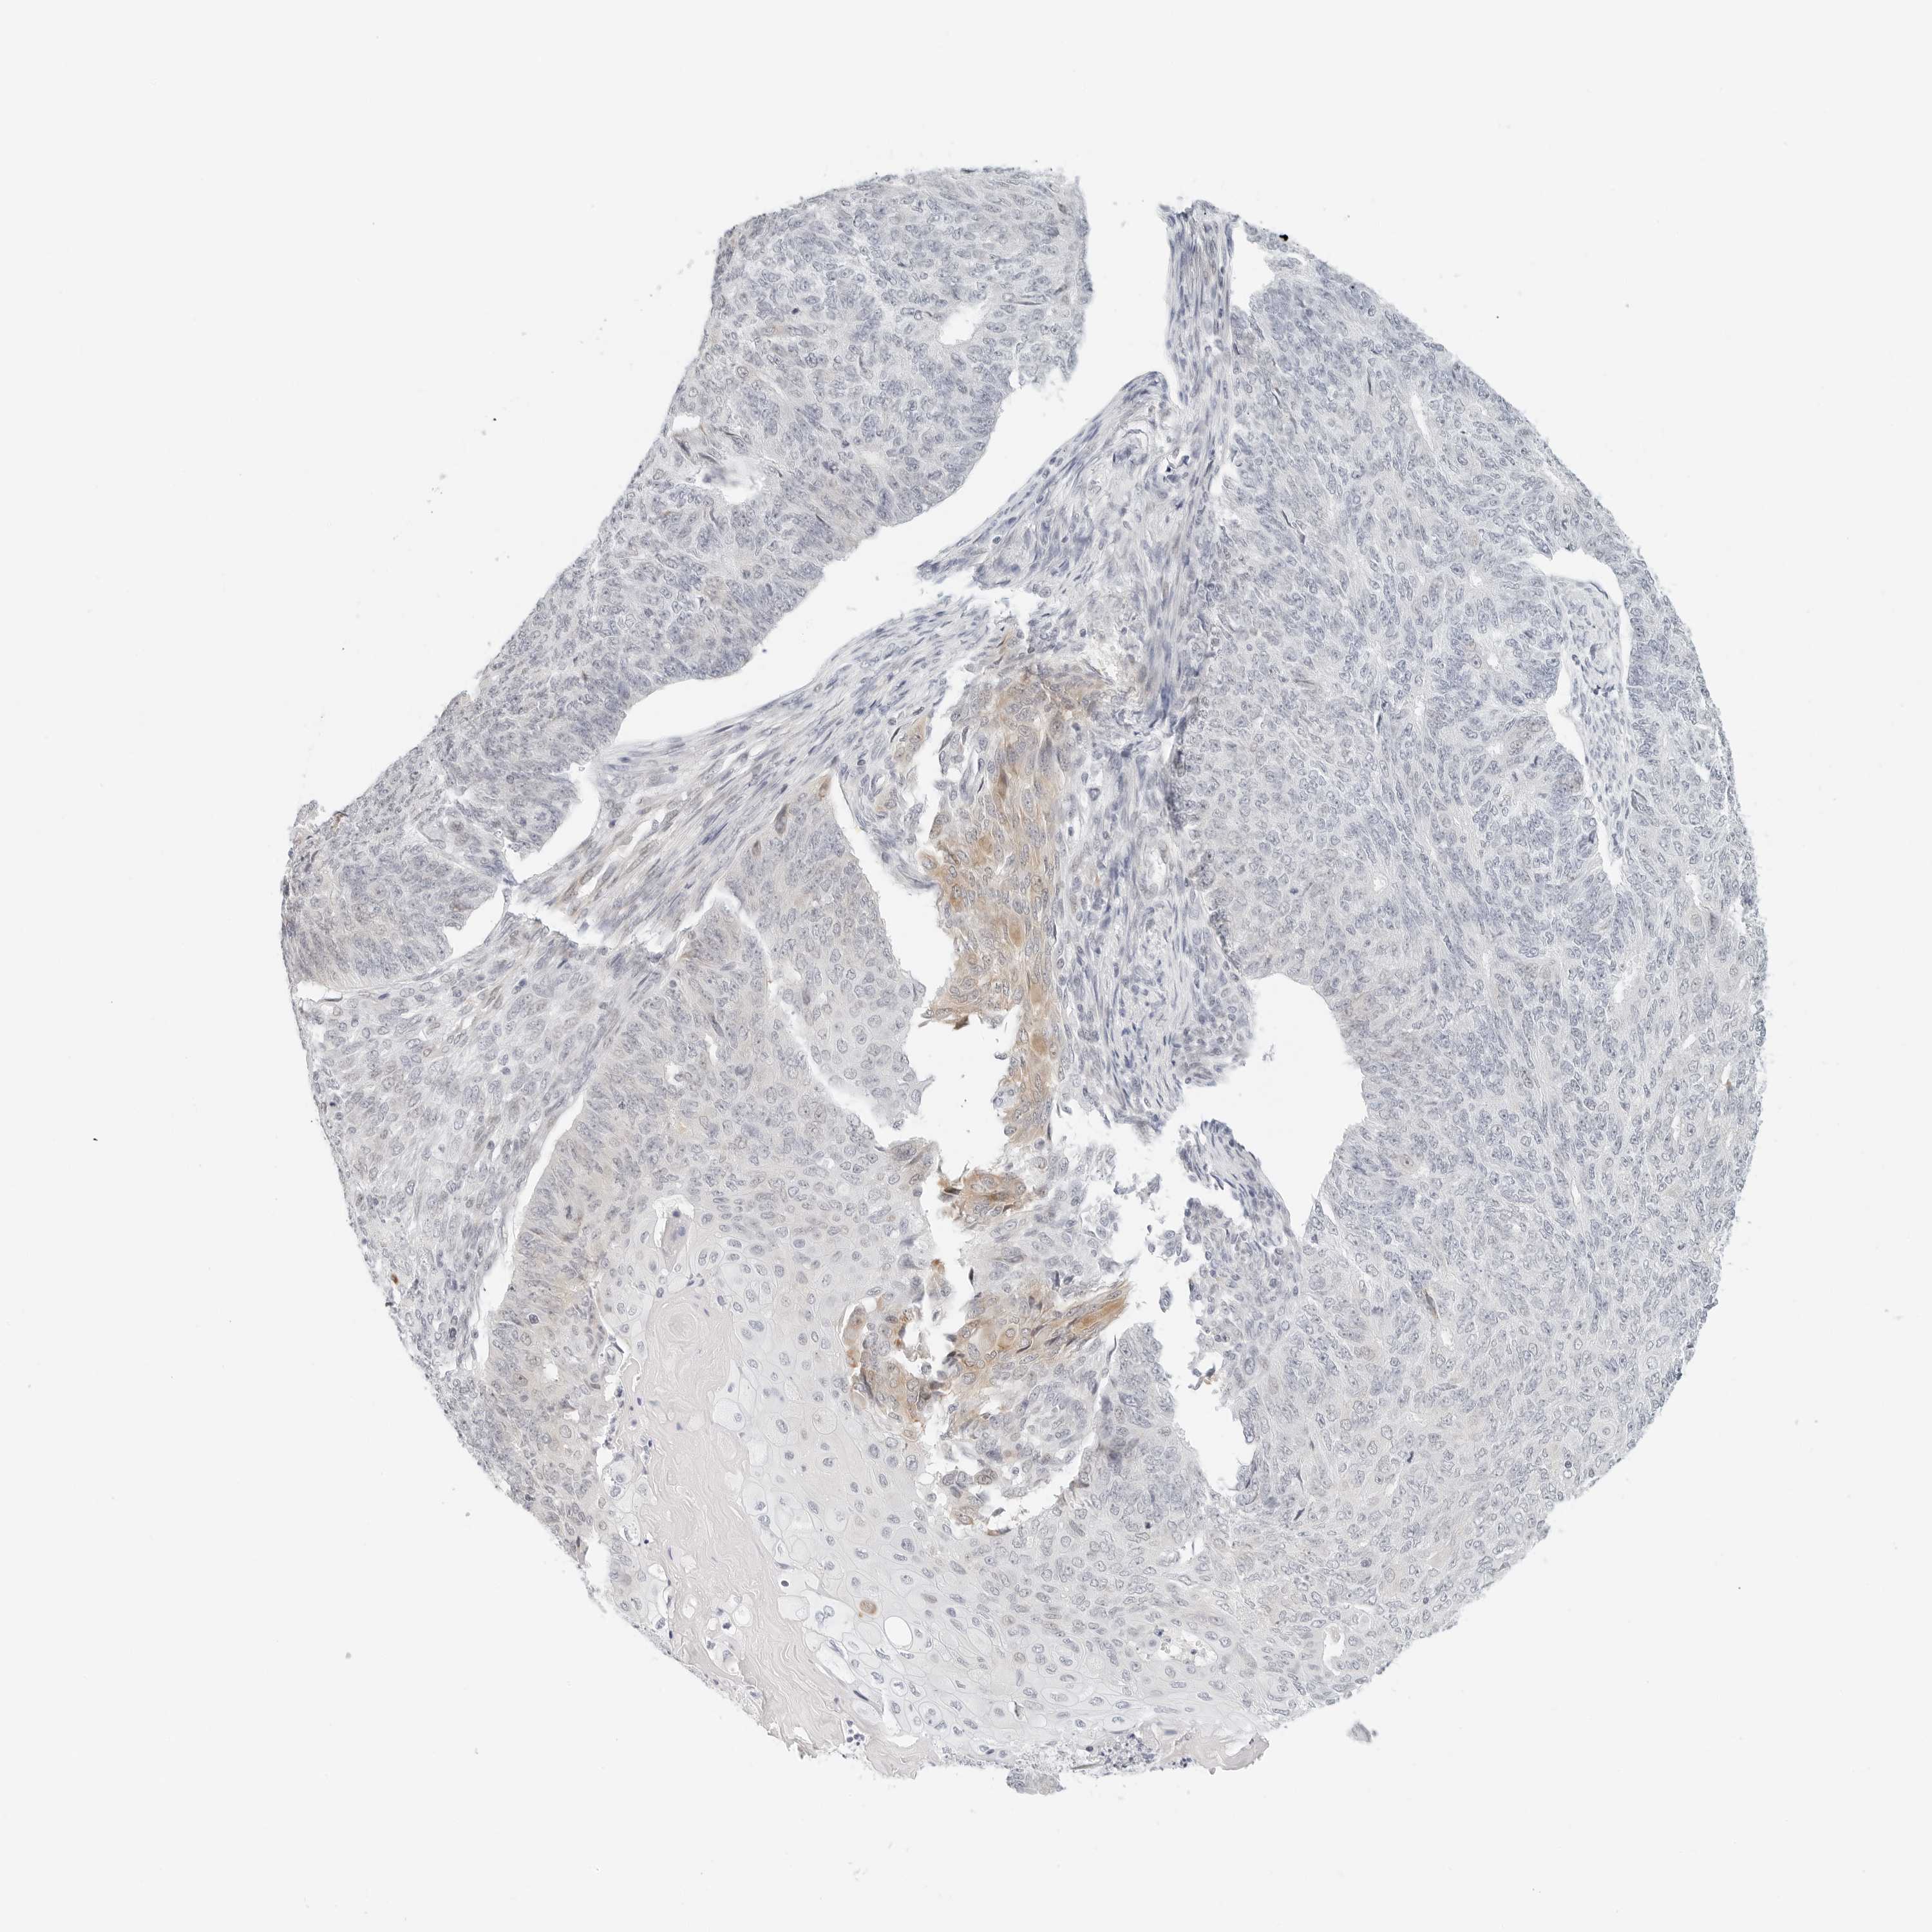

ENDOMETRIAL CANCER - Protein expressioni

A mouse-over function shows sample information and annotation data. Click on an image to view it in a full screen mode. Samples can be filtered based on level of antibody staining by selecting one or several of the following categories: high, medium, low and not detected. The assay and annotation is described here.

Note that samples used for immunohistochemistry by the Human Protein Atlas do not correspond to samples in the TCGA dataset.

Antibody stainingi

Antibody staining in the annotated cell types in the current human tissue is reported as not detected, low, medium, or high, based on conventional immunohistochemistry profiling in selected tissues. This score is based on the combination of the staining intensity and fraction of stained cells.

Each image is clickable and will lead to virtual microscopy that enables deeper exploration of all samples and also displays staining intensity scores, fraction scores and subcellular localization as well as patient and tissue information for each sample.

Antibody HPA028122

Staining

High

Medium

Low

Not detected

Intensity

Strong

Moderate

Weak

Negative

Quantity

>75%

75%-25%

<25%

None

Location

Nuclear

Cytoplasmic/membranous

Cytoplasmic/membranous,nuclear

Adenocarcinoma, NOS

Adenocarcinoma, metastatic, NOS